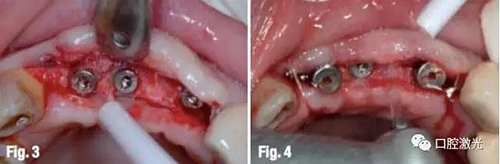

對手術(shù)區(qū)域?qū)嵤┚致楹?,利用激光對?1至22位置的牙齦進行內(nèi)切(圖2)。此處可以選用鉺激光(參數(shù)設(shè)定:70mJ/100微秒脈沖模式,20Hz,工作尖為400微米)也可以用半導(dǎo)體激光(參數(shù)設(shè)定:功率4W,連續(xù)模式,光纖直徑300或400微米,光纖尖須初始化)。隨后對整個齦瓣沿頰側(cè)和腭側(cè)翻開(圖3),通過觀察,決定僅保留11和22位置的種植體安裝愈合基臺。